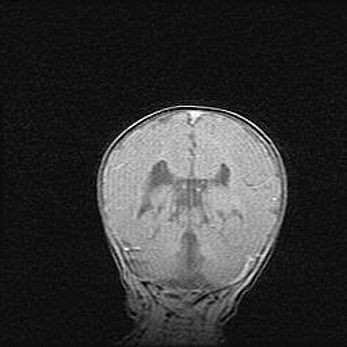

Неполная лизэнцефалия (пахигирия). Открытая гидроцефалия.

Возраст: 17 дней

Вес: 3110 г

Пол: мужской

Окружность головы: 33,5 см

Срок гестации: 35-36 недель

Лизэнцефалия—недоразвитие корковой пластинки и мозговых извилин в результате нарушения миграции нейронов коры. Поверхность мозговых полушарий гладкая. Микроскопически выявляется отсутствие нормальных слоев коры и скопление групп нейронов в подкорковом белом веществе.

Пахигирия—уменьшение числа вторичных извилин. В пораженном полушарии нервные клетки образуют толстый недифференцированный слой с неправильно расположенными нервными волокнами и группами гетеротопных клеток. Нервные клетки незрелые. Белое вещество истончено. При этом нередко аномально развит корково-спинномозговой путь.